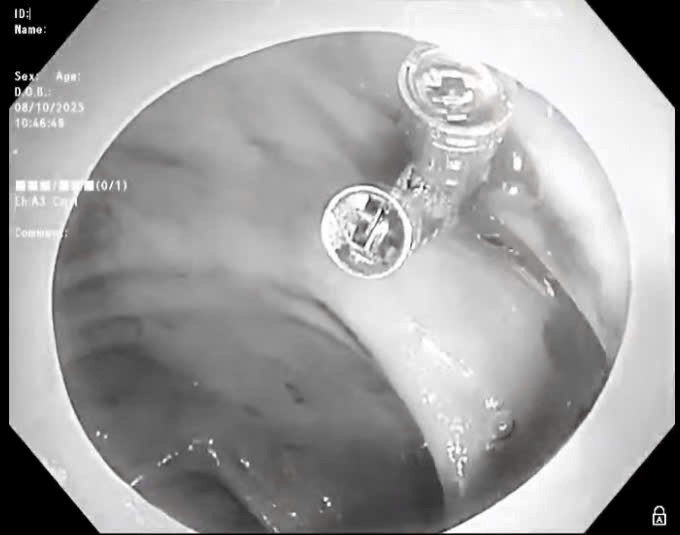

Bên cạnh đó, nhờ có nguồn máu an toàn và chất lượng, còn giúp cho ngành Y tế có thể triển khai, áp dụng nhiều kỹ thuật mới hiện đại như: ghép tạng, ghép tế bào gốc.